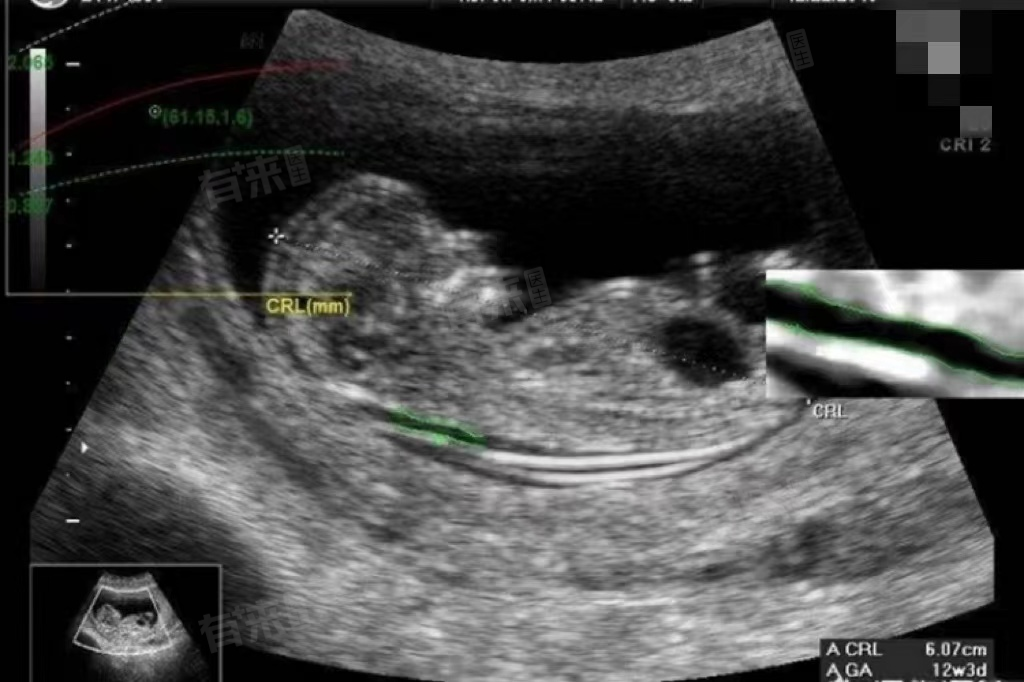

nt通常是指NT,做NT检查不需要憋尿。NT检查,全称为颈项透明层检查,是一种通过超声检查来评估胎儿颈后透明带厚度的产前筛查方法,可以在早期发现胎儿是否存在染色体异常或结构畸形的风险,NT检查一般在孕11-13周+6天进行。

- 在孕妇怀孕11周至13周+6天期间,胎儿已经逐渐长大成形,子宫内的羊水量也逐渐增多。这些条件使得超声检查能够清晰地显示胎儿的结构,而无需再通过膀胱充盈来作为透声窗。

- 随着医疗技术的不断进步,现代超声检查设备已经能够在无需憋尿的情况下,准确地进行胎儿颈项透明层的测量。因此,孕妇在进行NT检查时,无需刻意憋尿。